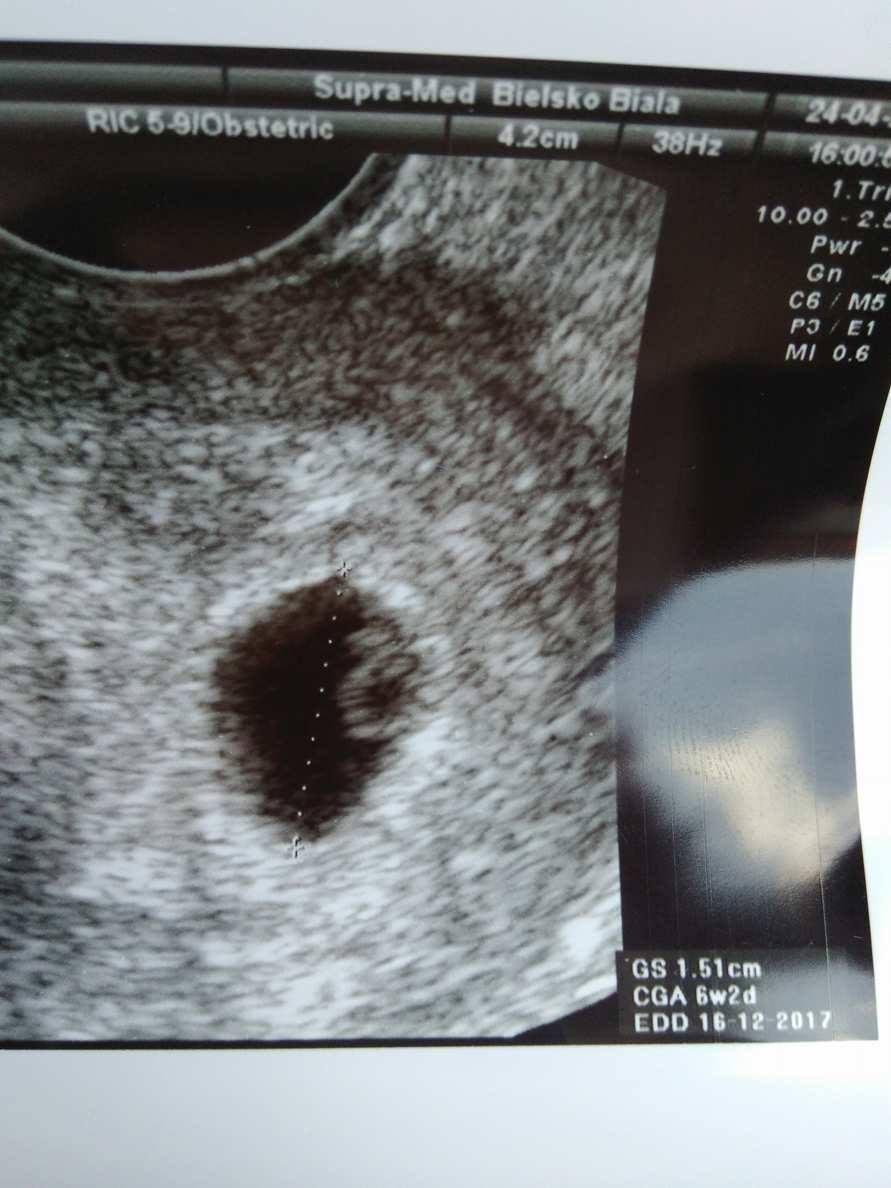

SlicznosciNa tym etapie ok, liczyłam już na zarodek z serduchem i niby coś tam zaczynało pulsować, ale powiedział, że zobaczymy za 3 tygodnie bobaska. Co do bólu powiedział, żebym zrobiła CRP jeśli faktycznie będą częste i mocne, ale jeśli po no-spie przechodzi szybko to według niego jelita. Wstawiam fotkę tutaj i w wątku wizytowym

Zobacz załącznik 803822